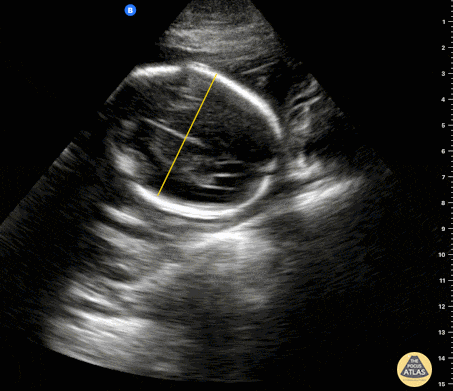

OB Dating Atlas - Week 15 - Biparietal Diameter (BPD)

A 26-year-old G4P3 with an unknown LMP and no prior prenatal care presents with vaginal spotting. She had a positive home UPT 3 weeks. On abdominal ultrasound, the biparietal diameter measures 2.79 cm consistent with a 15w0d IUP. General Rules: Used to estimate gestational age starting at 14w0d Both measurements should be taken in the transverse plane at the level of the of thalami and cavum septum pellucidum with no cerebellum in view BPD: measure from the outer edge of parietal bone to inner edge on the opposite side Accuracy3: ± 7 - 12 d